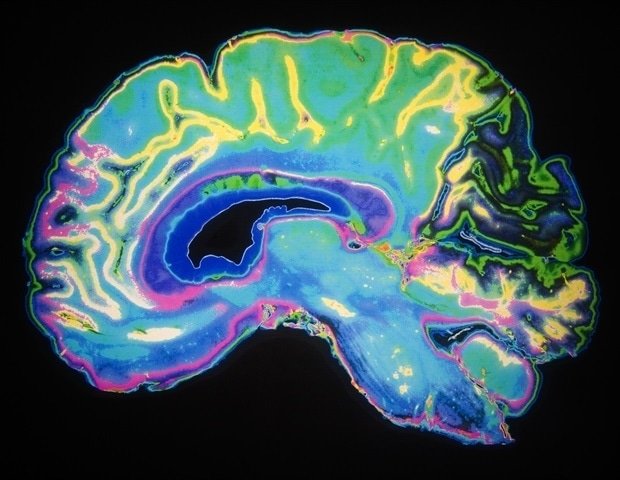

The IBC project was started in 2014 and was funded by the Human Brain Project. It aims to map how individual brains respond across a wide range of cognitive functions. By repeatedly scanning the same participants in a variety of tasks, from mathematics and spatial navigation to emotional recognition, reward processing, and working memory, the team is building an extremely rich resource for studying individual differences in brain organization.

With this release, the dataset now includes 67 tasks, 530 contrasts (comparisons between task conditions), and 188 cognitive concepts, creating an increasingly comprehensive foundation for fine-grained brain mapping and computational modeling.

IBC datasets are a valuable resource for modeling and understanding brain function. For example, it can be useful when validating new models of cognitive mapping or AI-driven models of neural activity. Because the same individual is scanned across a very wide range of tasks, researchers can investigate how different cognitive processes interact within a single brain and see how well brain models handle different tasks and contexts.